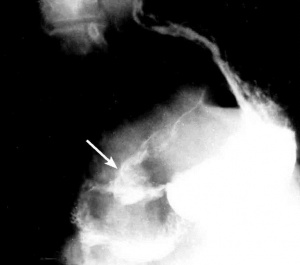

צילום הקיבה והתריסריון בעזרת חומר ניגוד

בליעת בריום תדגים את הכיב ב-80% מהחולים. זה יכול להיות כיב פעיל, או צלקת של כיב ישן. 95% מהכיבים הם בבצל התריסריון (בולבריים), ורק 5% מהם לאחר בצל התריסריון (פוסטבולבריים). מיעוטם ממוקמים בשוער (פילורוס). בצילום קשה למלא את הבצל מכיוון שהכיב מלווה בדלקת ובבצקת, ולפיכך ניתן לראות רק מילוי חלקי שלו. הדגמת המכתש (Crater) היא חשובה ביותר מכיוון שהיא מעידה על כיב פעיל. לעתים רואים את המכתש מוקף בהילה (Halo) של פגם מילוי, הנוצר עקב הבצקת שסביב הכיב.

הכיבים בצילום ממוקמים מלפנים, או מאחור, ונראים היטב חזיתית (En-face). כיבים לא פעילים גורמים לעווית וללייפת (הצטלקות) בדופן. בחולים הלוקים בכיבים כאלה ניתן לראות הרחבה של קפלי הרירית היוצאים כקרניים מהכיב - התכנסות קמטים. לעתים תיראה אסימטריה של הבצל (בולבוס), לפעמים סעיף מדומה(פסאודו דיברטיקולום), או עיוות של השוער (פילורוס) מלווה בהפרעות בהתרוקנות הקיבה.

ב-15% מהכיבים הפוסט-בולבריים (רובם נמצאים פרוקסימלית לפפילה), ניתן למצוא בנוסף גם כיבים בולברים - כיבים נושקים (Kissing ulcer). עם ריפוי הכיב, תיראה הפחתה בקוטר הכיב עד היעלמותו. בשלבים אלה תיראה בצילום צורה של עלה תלתן, כביטוי לצלקת מקומית ופיברוזיס באזור הכיב. אין די בהדגמת הפגם בצילום אחד, אלא יש להדגימו בכמה צילומים (תצלומים 4.3-1.3). מאז נכנסה הגסטרוסקופיה צילום הקיבה והתריסריון איבד מחשיבותו ולא מבוצע יותר כבדיקת שגרה.